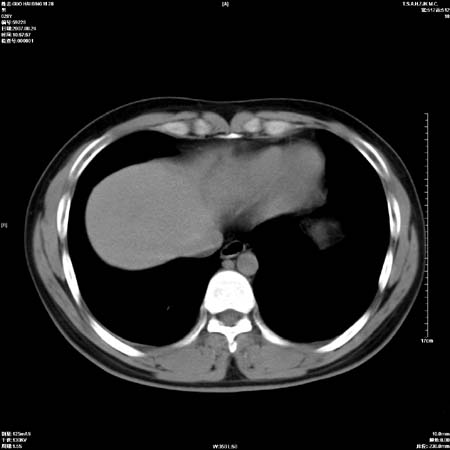

左肺门区软组织肿块,左肺上叶支气管开口消失,纵隔内见肿大淋巴结,考虑左中心型肺部,可以做纤支镜取病理确认.

左肺肺门区肿块影,分叶明显,左肺上叶支气管开口受压,纵隔内见肿大淋巴结,考虑左中心型肺癌。

支持左上叶中央型肺癌伴纵隔淋巴结转移.

左上叶中央型肺癌伴纵隔淋巴结转移

左侧肺门区见一块状病灶可见分叶,纵隔内及左肺门见肿大淋巴结,应该是周围型肺癌而不是中心型肺癌,原因有以下2点,1未见阻塞肺气肿和阻塞性炎症,这么大肿块如果是中心型肺癌就是未分化型或小细胞型肺癌不出现阻塞性肺不张也应该有阻塞炎症或阻塞性肺气肿,2如果是中心型肺癌临床出现最早的症状是咳嗽(此时可无任何异常影象),而此人这么大肿块只有背部隐痛是体检才发现无法解释.

肿块形态影像支持左上叶中央型肺癌伴纵隔淋巴结转移。

左肺中心型肺癌并纵隔淋巴结转移!考虑为小细胞肺癌,没有手术机会了,只能进行放化了,疗效不错,但极易复发。没办法,现在肿瘤年轻化越来越明显了。